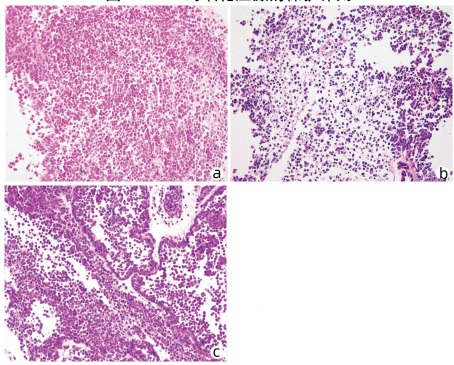

Effect of Shuganning injection on the model of cholestasis - type chlorpromazine - induced liver injury constructed by a new tissue - engineered liver

Long HUANG, Yu CHEN, Qiao WU, Zhongping DUAN

2022, 38(3): 587-593. DOI: 10.3969/j.issn.1001-5256.2022.03.018

Abstract(1201) HTML (437) PDF (4120KB)(53)

Abstract:

Objective  To investigate the effect of Shuganning injection (SGN) in alleviating drug-induced cholestasis and the possible mechanisms involved.  Methods  The liver of Sprague-Dawley rats was decellularized to prepare collagen scaffolds, and then the scaffolds were recellularized with human HepG2 cells to obtain the tissue-engineered liver (normal control group). The tissue-engineered liver was perfused with 10 μmol/L chlorpromazine (CPZ) and bile salt mixture to establish a model of drug-induced cholestasis (CPZ group), and the model was further treated with Shuganning injection (103-fold dilution) as the injury protection group (SGN+CPZ group). The markers for hepatocellular injury [alanine aminotransferase (ALT), aspartate aminotransferase (AST), lactate dehydrogenase (LDH), and alkaline phosphatase (ALP)] and the antioxidant and oxidative stress markers [glutathione (GSH), malondialdehyde (MDA), superoxide dismutase (SOD), and reactive oxygen species (ROS)] were measured for all groups, and the normal control group, the CPZ group, and the SGN+CPZ group were compared in terms of the mRNA and protein expression levels of the enzymes associated with liver bile salt metabolism and the enzymes associated with hepatic cholestasis. HE staining was performed to observe liver pathology. A one-way analysis of variance was used for comparison of continuous data between multiple groups, and the least significant difference t-test was used for further comparison between two groups.  Results  Compared with the CPZ group, the SGN+CPZ group had significant reductions in the markers for hepatocellular injury ALT, AST, LDH, and ALP (all P < 0.000 1), significant increases in the oxidative stress markers GSH and SOD (P < 0.000 1 and P < 0.001), and significant reductions in the markers MDA and ROS (P < 0.000 1 and P < 0.001). Compared with the CPZ group, the SGN+CPZ group had significant reductions in the mRNA expression levels of cholesterol 7α-hydroxylase (CYP7A1) and sterol 12α-hydroxylase (CPY8B1) in hepatocytes (all P < 0.001) and significant increases in the mRNA expression levels of farnesoid X receptor (FXR), small heterodimeric partner (SHP), bile salt export pump (BSEP), and multidrug resistance-associated protein 2 (MRP2) (P < 0.000 1, P < 0.01, P < 0.000 1, and P < 0.000 1). HE staining showed that compared with the CPZ group, the SGN+CPZ group had a significant reduction in hepatocyte injury and a significant increase in the number of cells.  Conclusion  Shuganning injection can alleviate drug-induced cholestatic liver injury caused by chlorpromazine, and it exerts a protective effect by activating FXR in hepatocytes and increasing the expression of SHP to regulate bile salt balance. It also inhibits CYP7A1 and CYP8B1 to reduce the synthesis of hydrophobic bile acids and upregulates the expression of BSEP and MRP2 to promote the excretion of bile salts.